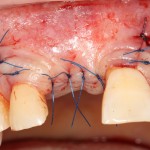

Если после этого BioGide намочить физраствором, им легко укрыть получившийся объем:

Для надежности можно зафиксировать пинами:

Ну и, швы: